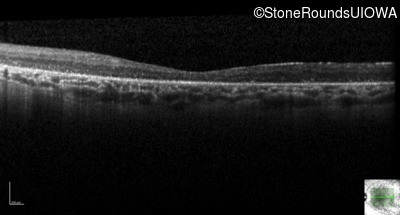

Optical Coherence Tomography - Right - 10/140 sc

Exemplar / OCT Stack

Optical Coherence Tomography - Left - 10/180 sc